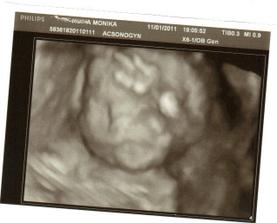

✿♥♥♥♥Bude to dievčatko!!!!! ♥♥♥♥✿

Bude to Stella 🙂

krasne 3D sono 🙂